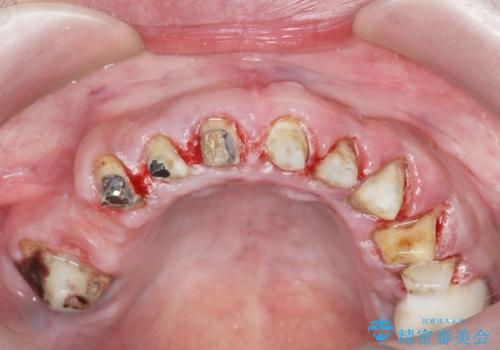

- 「セラミック治療を他院で受けたが、それ以来歯ぐきが腫れ違和感がある、改善してほしい。」と歯ぐきの状態改善を希望され来院されました。

歯周組織検査を行うと歯ぐきからは容易に出血し、X線検査より歯とセラミッククラウンの適合が悪い(ピッタリと合っていない)状態が示唆され、歯ぐきの炎症を惹起している状態でした。

セラミッククラウンを除去し仮歯を装着し、歯周外科手術を行い歯ぐきの状態を改善したのち、適合の良いセラミッククラウンを再作製をする治療計画としました。

見た目の良いクラウンが装着されていても、歯ぐきの状態が悪ければ違和感や歯ぐきの腫れ、臭いの元となっていることが多く見られます。